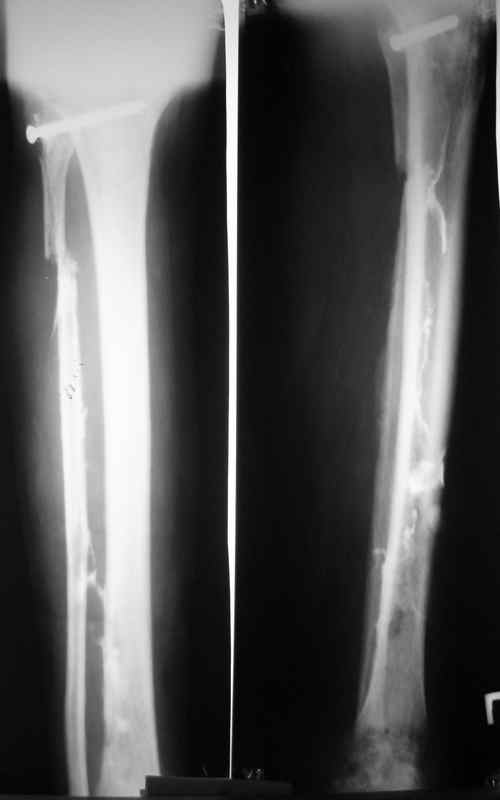

Доброго времени суток, коллеги! Сегодня поступил больной с остеомиелитом голени, 29 лет. Травма - январь 2007 года, <Открытый перелом малоберцевой кости,с повреждением малоберцевого нерва>. Первичных снимков нет. лечился в одной из районных больниц xUSSR. Обратился ко мне в сентябре 2007 года, сжалобами на наличие свищей,неопорность конечности.Был направлен после выполнения фистулографии (см. фото) в областной центр по лечению остеомиелита. Там была выполнено 2 операции: резекция малоберцевой кости, и повторный дебридмент. Последнее вмешательство около месяца назад. Послеоперационные снимки на фото. В течении месяца получал перевязки, и иньекции Бициллина- 5.Выписки больной не предоставил, вся информация с его слов. Опять же с его слов были рекомендованы перевязки с раствором димексида. На момент поступления раны и свищи хорошо видно на картинке, в дне раны кость жёлтого цвета, из раны гнойное отделяемое, с прямо таки неприятным запахом. (посев возьму завтра, но скорее всего там будет синегнойная, MRSA ). Стопа в эквинусе, активных движений нет, конечность неопорна. В связи с тем, что больной лечился в вышестоящей больнице, прошу скорректировать план лечения. Мой план: выполнить полноценный дебридмент, лаваж, <бусы>, рану зашить с дренажами по Редону. При выявлении поражения большеберцевой кости более 2\3 диаметра сегментарная резекция с последующим замещением дефекта по Илизарову. Активная ЛФК для голеностопа.